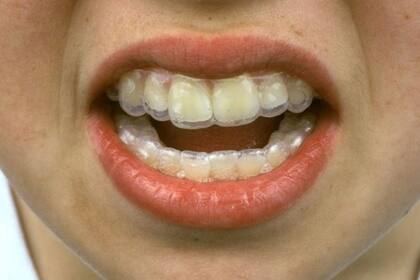

La presión por mostrar sonrisas perfectas en redes sociales como Instagram está generando graves problemas en los dientes de gente que optaron por el uso de aparatos transparentes o “alineadores” comprados en Internet.

La empresa estadounidense de ortodoncia a distancia ofrecía alineadores transparentes por unos US$2000 sin necesidad de acudir en persona a un dentista.

En la odontología tradicional, los aparatos metálicos y los alineadores transparentes los colocan los propios odontólogos y ortodoncistas, o un auxiliar ortodoncista cualificado, luego de una consulta en persona.